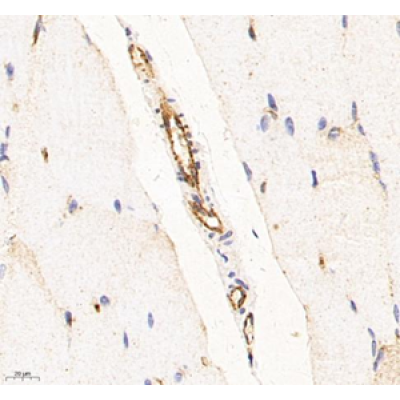

| IHC analysis of CD31 (GB12063). Sample: Rat skeletal muscle (Paraffin), 4% PFA (G1101) 12-24h. Antigen retrieval: Citrate buffer (pH 6.0) (G1201), pressure cooker 2min. Blocking buffer: 3% BSA in PBS (GC305010), RT, 30min. Primary antibody: 1: 200, 4°C overnight. Secondary antibody: HRP Goat Anti-Mouse lgG (GB23301), 1: 200 RT 1h. |